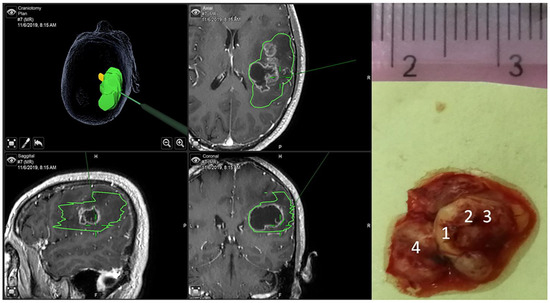

A Handheld Visible Resonance Raman Analyzer Used in Intraoperative Detection of Human Glioma

by Liang Zhang, Yan Zhou, Binlin Wu, Shengjia Zhang, Ke Zhu, Cheng-Hui Liu, Xinguang Yu and Robert R. Alfano

Cancers 2023, 15(6), 1752; https://doi.org/10.3390/cancers15061752 - 14 Mar 2023

Cited by 18 | Viewed by 3305

Abstract

There is still a lack of reliable intraoperative tools for glioma diagnosis and to guide the maximal safe resection of glioma. We report continuing work on the optical biopsy method to detect glioma grades and assess glioma boundaries intraoperatively using the VRR-LRRTM [...] Read more.

There is still a lack of reliable intraoperative tools for glioma diagnosis and to guide the maximal safe resection of glioma. We report continuing work on the optical biopsy method to detect glioma grades and assess glioma boundaries intraoperatively using the VRR-LRRTM Raman analyzer, which is based on the visible resonance Raman spectroscopy (VRR) technique. A total of 2220 VRR spectra were collected during surgeries from 63 unprocessed fresh glioma tissues using the VRR-LRRTM Raman analyzer. After the VRR spectral analysis, we found differences in the native molecules in the fingerprint region and in the high-wavenumber region, and differences between normal (control) and different grades of glioma tissues. A principal component analysis–support vector machine (PCA-SVM) machine learning method was used to distinguish glioma tissues from normal tissues and different glioma grades. The accuracy in identifying glioma from normal tissue was over 80%, compared with the gold standard of histopathology reports of glioma. The VRR-LRRTM Raman analyzer may be a new label-free, real-time optical molecular pathology tool aiding in the intraoperative detection of glioma and identification of tumor boundaries, thus helping to guide maximal safe glioma removal and adjacent healthy tissue preservation. Full article